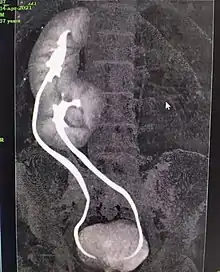

Grossesse ectopique, ou extra-utérine

Lors d'une grossesse normale, l'embryon s'implante généralement dans le haut de l'utérus. Cependant, il arrive parfois que l'embryon commence son développement à un autre endroit, le plus fréquent étant dans la trompe. Ce type de grossesse, extra-utérine, est dit « ectopique ». Le bébé n'est en général pas viable et ce phénomène peut être très dangereux pour la mère.